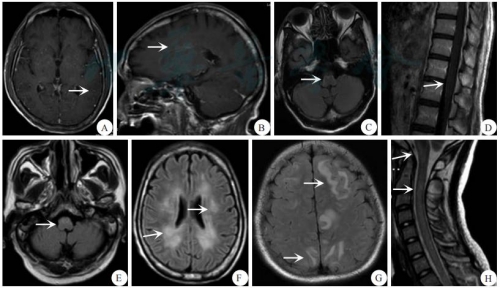

本组12例患者行头颅 MRI 检查均发现脑实质异常病灶,T2/FLAIR 序列表现为点状、斑片状异常高信号,伴有轻微点状强化。病灶主要位于脑干(10例)、基底节区(8例)、脑室旁白质(7例)、丘脑(6例)、皮层(5例)、胼胝体(4例)、小脑(2例)、视束(1例),其中脑干病灶中有 7例累及延髓。2例患者出现典型的垂直于侧脑室的脑白质内血管周围线性放射性线样征,10例患者表现出软脑膜异常强化。8例患者行全脊髓MRI平扫+增强扫描检查,其中7例可见异常病灶,表现为斑片状、点状异常信号改变,但未见长节段病灶。3例累及颈胸段脊髓,1例仅累及下段胸髓,1例仅累及颈髓,2例累及脊髓圆锥。6例出现全脊髓膜线样强化。具体内容见表1。典型病例的MRI检查资料见图1。

A:双侧大脑半球脑沟内广泛线状强化;B:侧脑室周围放射样线样强化;C:延髓周缘明显线样强化;D:脊髓周围软脊膜(脊髓圆锥)异常线样强化;E:延髓斑片状FLAIR序列高信号;F:双侧基底节区、胼胝体、双侧放射冠区多发片状及斑片状FLAIR序列高信号;G:双侧额顶枕叶皮层及皮层下不对称斑片状FLAIR序列高信号;H:延髓、颈髓内多发条片状、斑片状T2W1高信号;箭头所示为病灶。

图1 1例典型重症自身免疫性胶质纤维酸性蛋白星形胶质细胞病患者的MRI表现